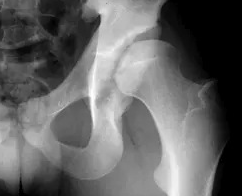

Poznamo dva osnovna tipa utesnitve kolčnega sklepa (slika 2).

Slika 2. Utesnitev kolčnega sklepa – rentgenska slika

a – stegnenični (angl. cam) tip utesnitve; glavica stegnenice ni okrogla, v sprednjem delu je izbočena (označeno z belo puščico)

b – acetabularni (angl. pincer) tip utesnitve; acetabulum je globok

Stegnenični tip utesnitve (angl. cam ali pistol-grip) je posledica neokrogle oblike glavice stegnenice in je pogost pri mlajših moških. Acetabularni tip utesnitve (angl. pincer) je posledica nagiba površine acetabula nazaj (retroverzije) ali povečane poglobljenosti acetabula. Najpogosteje prizadene ženske v srednjih letih. V praksi se pogosto srečamo s pacienti, ki imajo kombinacijo obeh omenjenih tipov utesnitve kolka. Natančen razlog za nastanek nepravilne oblike, ki povzroči utesnitveni sindrom kolka, ni povsem znan. Zadnje raziskave so pokazale, da so lahko vzrok za to preobremenitve rastnega hrustanca v obdobju hitre rasti otroka. Verjetno je zato pri bivših športnikih utesnitveni sindrom kolka bolj pogost.